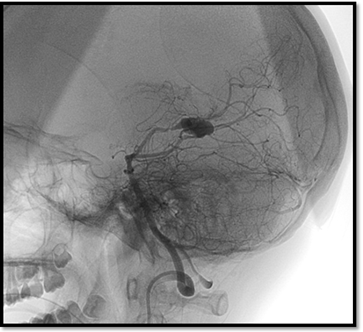

Se efectuó una craneotomía suboccipital lateral con evacuación del absceso cerebeloso. En la evolución, el paciente presentó un hematoma espontáneo secundario a la rotura de un aneurisma fusiforme del segmento P3 de la arteria cerebral posterior, confirmado por angiografía digital. El hallazgo fue interpretado como un aneurisma micótico, por lo que se realizó tratamiento endovascular. La resonancia magnética posterior a la embolización no evidenció aneurisma residual (Figuras 1 y 2).

Figura 1. Angiografía digital diagnóstica de vasos intracraneales. Se evidencia dilatación aneurismática del segmento P3 de arteria cerebral posterior derecha.